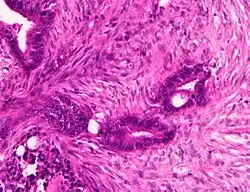

Adenocarcinoma is a malignant epithelial tumor, originating from superficial glandular epithelial cells lining the colon and rectum. It invades the wall, infiltrating the muscularis mucosae layer, the submucosa, and then the muscularis propria. Tumor cells describe irregular tubular structures, harboring pluristratification, multiple lumens, reduced stroma ("back to back" aspect). Sometimes, tumor cells are discohesive and secrete mucus, which invades the interstitium producing large pools of mucus. This occurs in mucinous adenocarcinoma, in which cells are poorly differentiated. If the mucus remains inside the tumor cell, it pushes the nucleus at the periphery, this occurs in "signet-ring cell." Depending on glandular architecture, cellular pleomorphism, and mucosecretion of the predominant pattern, adenocarcinoma may present three degrees of differentiation: well, moderately, and poorly differentiated.[5]

- Invasive adenocarcinoma commonly displays:[6]

- Varying degrees of gland formation with tall columnar cells

- Frequently desmoplasia

- Dirty necrosis, consisting of extensive central necrosis with granular eosinophilic karyorrhectic cell detritus.[6][7] It is located within the glandular lumina,[7] or often with a garland of cribriform glands in their vicinity.[6]

-

Colorectal carcinoma with desmoplastic reaction (*) -

Dirty necrosis